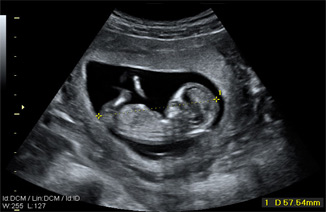

Hay un caso en el que la FPP no se calcula de acuerdo con la fecha de última regla (FUR). Esto sucede cuando la edad gestacional ecográfica estimada en la ecografía del primer trimestre es discrepante con la calculada por la FUR en al menos 1 semana. Insistimos en el concepto del cálculo de la edad gestacional por la ecografía del primer trimestre, ya que es en este momento en el que las medidas fetales proporcionan un menor margen de error, de aproximadamente +/- 3 días.

Sin embargo, el cálculo gestacional realizado en ecografías posteriores tiene un margen de error más amplio. Por ejemplo, en el tercer trimestre este error puede ser de hasta +/- 2-3 semanas puesto que existe mucha mayor variabilidad de unos fetos a otros en este momento que cuando comienza su desarrollo.

La mayoría de los informes ecográficos del tercer trimestre equipara las mediciones fetales con las semanas de edad gestacional a la que corresponden esas mediciones como media.